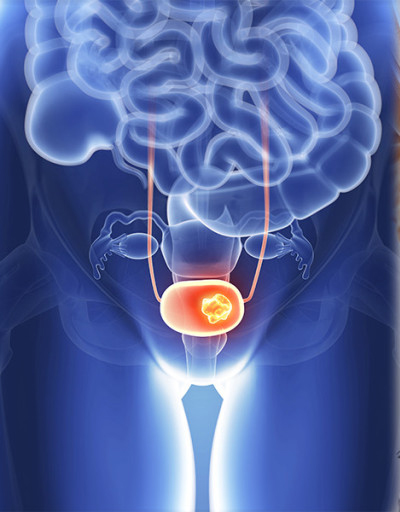

전립선암이 발생한 것을 모르고 전이로 인한 증상을 통하여 암을 발견하는 그럴 경우가 적지 않는다. 일부 환자는 조기에 원격 전이가 나타나기도 해요. 이러한 그럴 때에는 전립선 주변 부위를 광범위하게 침범하기도 합니다.. 골반 림프절이나 골반뼈, 척추뼈 등이 잘 전이되는 곳이에요.

8. 국소 침윤

전립선암의 진행이 많이 된 그럴 경우, 광범위하게 전이가 되었을 가능성을 보이는 것으로 암이 직장을 침범한 그럴 경우 혹은 성적인 자극이 없이 음경이 계속하여 발기되어 있는 증상을 보이기도 합니다.. 암이 직장을 침범한 그럴 경우라면 변비가 생기거나 복통이 발생하며, 직장에서의 출혈 등이 있기도 합니다..